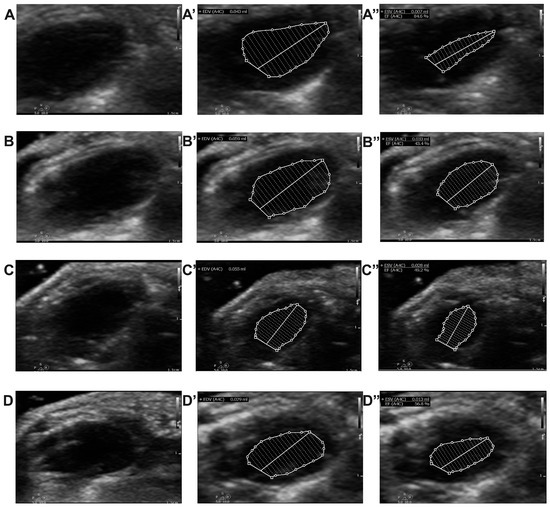

2.4. Effect of Chitosan and Dapagliflozin on LV Dimensions and Functions

4.3. Echocardiography